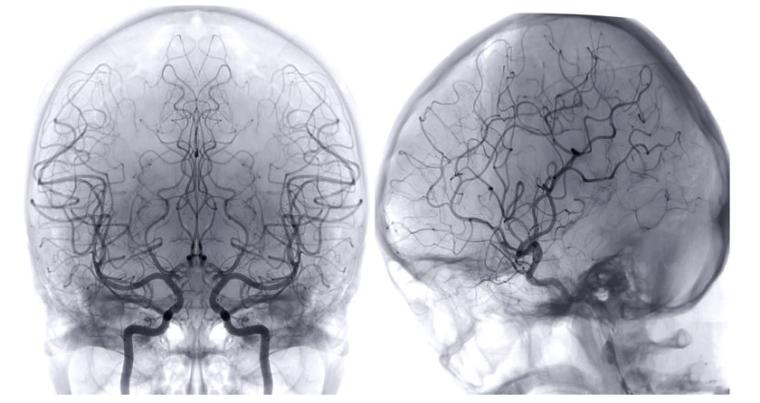

Der Empa-Forscher Peter Nirmalraj und sein Team wollen ein umfassendes Verständnis von Blutgerinnseln bei Patienten mit Schlaganfall, COVID-Komplikationen oder mit seltenen Arten von Demenz wie der vaskulären Demenz, die durch Schlaganfälle ausgelöst wird, erarbeiten. Gemeinsam mit der Neurologin und Schlaganfallforscherin Susanne Wegener von der Universität Zürich nutzen die Forschenden unterschiedliche Bildgebungs- und Messmethoden, um Blutklumpen von Schlaganfallpatienten genau anhand ihrer Zusammensetzung, Form und Größe zu charakterisieren. Zudem untersuchen sie, wie verschiedene Gerinnsel auf unterschiedliche Behandlungsmethoden reagieren.